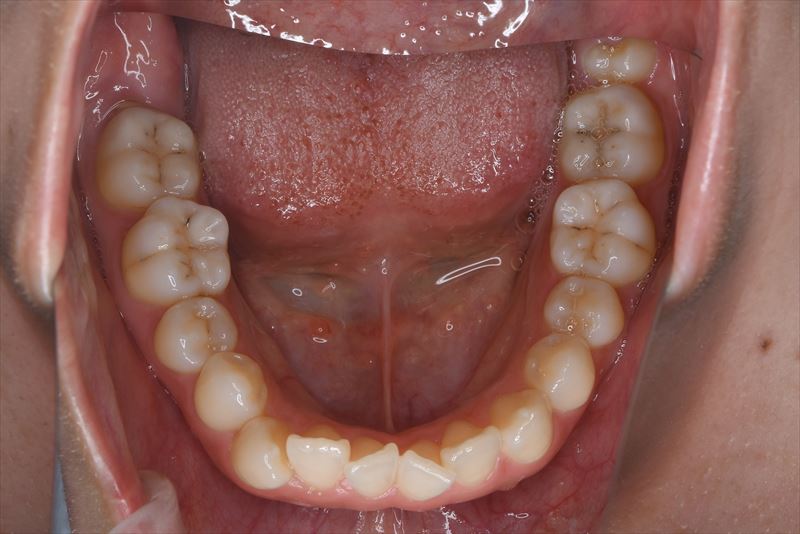

治療前

症状

叢生、口唇の突出

上顎両側4番抜歯、下顎両側4番抜歯、下顎両側8番抜歯

臼歯のみの咬合、口唇の閉鎖が難しい状況でした。抜歯を行い前歯を牽引することで、良好な側貌と緊密な咬合を獲得できました。